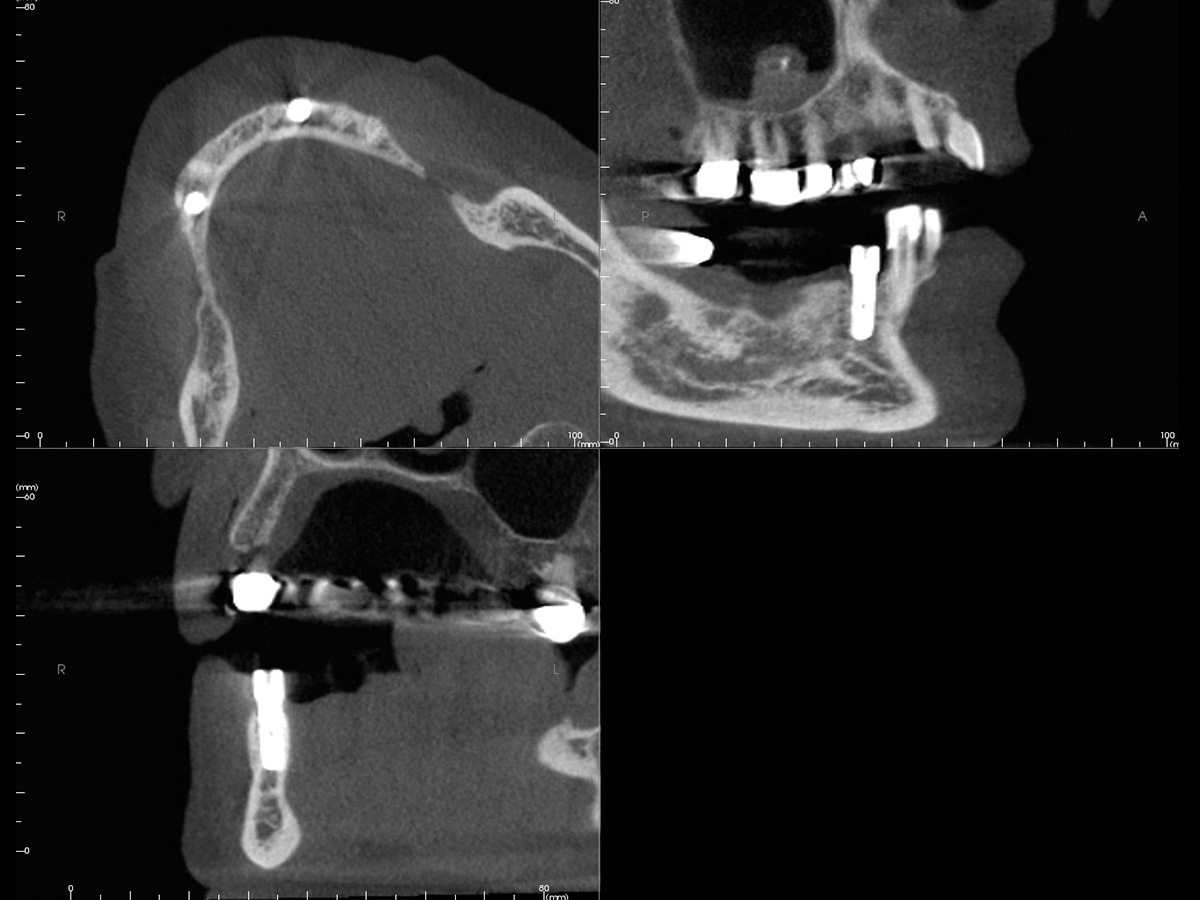

Abbildung 10a

Kontrollbilder...

Abbildung 10b

nach...

Abbildung 10c

6 Monaten.